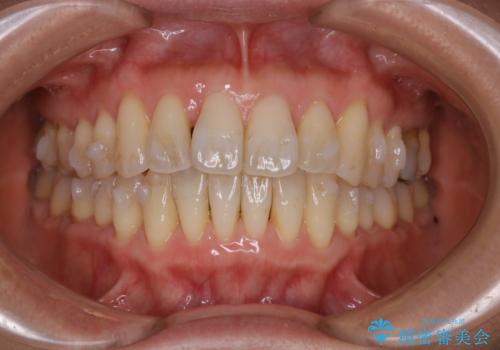

歯ぐき、骨が薄い方のマウスピース矯正治療 非抜歯でもIPR(歯を削る処置)で口元に変化を

- 歯ぐきと骨が薄く、他院にて大きな矯正治療を断られた患者様です。

ワイヤー治療で行う場合、抜歯治療が第一選択となりますが、

骨と歯茎の状態を考慮した場合、抜歯をして大きく動かすことは避けたいと考えました。

そこで、インビザライン矯正で非抜歯で行うことを提案させて頂きました。

インビザラインによる非抜歯矯正を行いました。

IPRと呼ばれる、歯と歯の間を削る処置を行い、

がたつきを改善し歯を内側に入れることに成功しました。